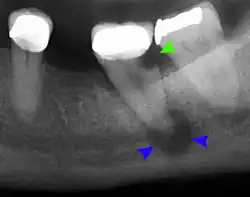

The periodontal ligament becomes inflamed and there may be pain when biting or tapping on the tooth. On an X-ray, bone resorption appears as a radiolucent area around the end of the root, although this does not manifest immediately.[10]: 228 Acute apical periodontitis is characterized by well-localized, spontaneous, persistent, moderate to severe pain.[6]: 125–135 The alveolar process may be tender to palpation over the roots. The tooth may be raised in the socket and feel more prominent than the adjacent teeth.[6]: 125–135

- Radiographs utilized to find dental caries and bone loss laterally or at the apex.